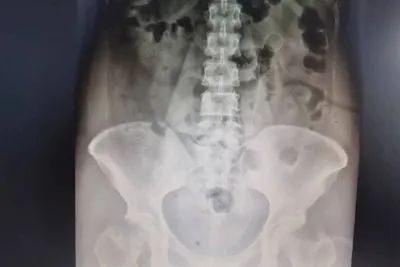

泌尿系CT及逆行造影检查,示:左肾重度积水、肾盂扩张,输尿管肾盂连接部以下无扩张积水,肾盂呈肾内型肾盂。